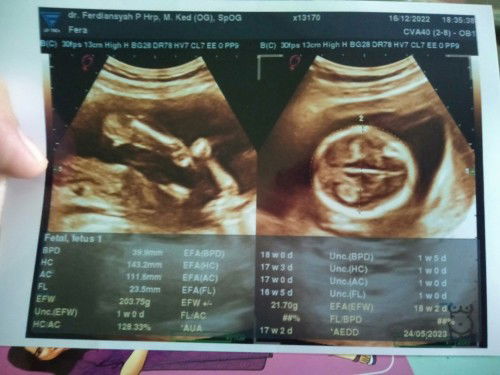

Bun mau tanya donk , saya kmrn USG usia kehamilan saya 17 week 2 day sesuai HPHT karna dari awal usg dokter uda bilang kata nya letak placenta dan janin di bawah saya uda panik duluan , maklum ini kehamilan kedua saya setelah yg pertama keguguran karna BO , saya jd blank mo nanya2 yg lain .. bunda2 bisa bca hasil usg saya disini ga .. kmrn yg saya tangkep cuma bbj kurang gt suruh makan banyak protein , dan djj jg katanya normal .. lalu ada saran biar placenta naik ga bun soalnya emang saya ngerasain agak sering kram di bagian atas vagina walaupun jarang2 kerasanya , sampai sekarang jg masih minum penguat kandungan karna pernah nyoba ga minum sehari kluar flek ga parah sih cuma segaris kaya rambut gt tp cuma sehari besok nya ilang tp skrg uda jarang kluar lagi .. mohon d jawab ya bun yg tau .. trimakasih sebelumnya #seriusnanya #bantusharing